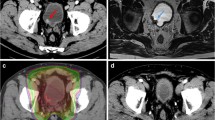

Daily imaging identifies changes in organ size, shape and position between fractions; allowing margins to be reduced without missing the bladder [17]. The MR Linac integrates a magnetic resonance (MR) scanner with a linear accelerator (Linac) that delivers radiotherapy. It allows on treatment imaging with better differentiation of soft tissue structures than a conventional Linac (Fig. 1) potentially allowing further reduction of margins. In addition, newer techniques of radiation delivery such as VMAT allow better ‘conformality’ of the high-dose region around the intended target. Before reducing treatment field though, a potential contribution of ‘incidental dose’ delivered to surrounding lymph nodes on disease control should be considered. Rates of occult lymph node metastases of around 25% have been seen in surgical series in patients staged as N0 on imaging [18], but the rate of pelvic node relapse in BC2001 (in which radiotherapy was delivered to bladder only and pelvic lymph nodes not treated) was only 5.8% (21/360) [14]. An explanation for this disparity could be the incidental delivery of clinically meaningful radiation dose to adjacent lymph nodes with bladder-only techniques [19]. Elective pelvic nodal radiotherapy has failed to demonstrate benefit in BC [20] which again could be due to incidental dose to lymph nodes with bladder-only radiotherapy. Therefore, reduction in expansion margins around the bladder should be performed with caution.

Patient with urothelial cell carcinoma of the bladder and a long-term urinary catheter receiving 55 Gy in 20 fractions of radiotherapy with concurrent BCON (carbogen and nicotinamide). Images acquired on the MR Linac with axial (A), coronal (B) and sagittal (C) views shown. Bladder Clinical Target Volume (CTV, royal blue) is expanded to bladder planning target volume (PTV, light blue). Isodose lines from the radiotherapy plan are shown with good conformality of the 95% isodose line (52.25 Gy, yellow) around bladder PTV